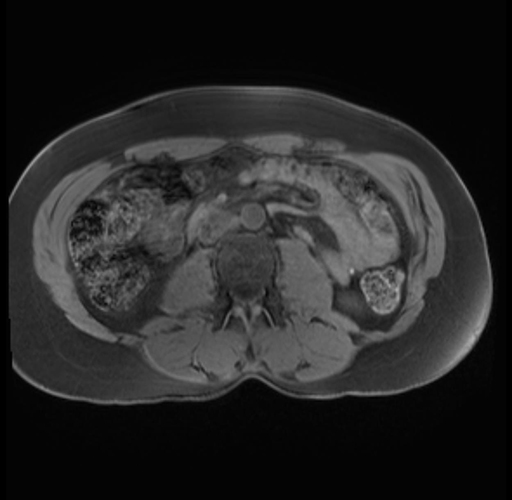

Imaging Analysis

Look through the patient's CT scan to identify any areas of concern for the necessary procedure.

Based on your CT findings, which issue(s) are present and would give reason for "planned slowing down moment(s)" in this case?